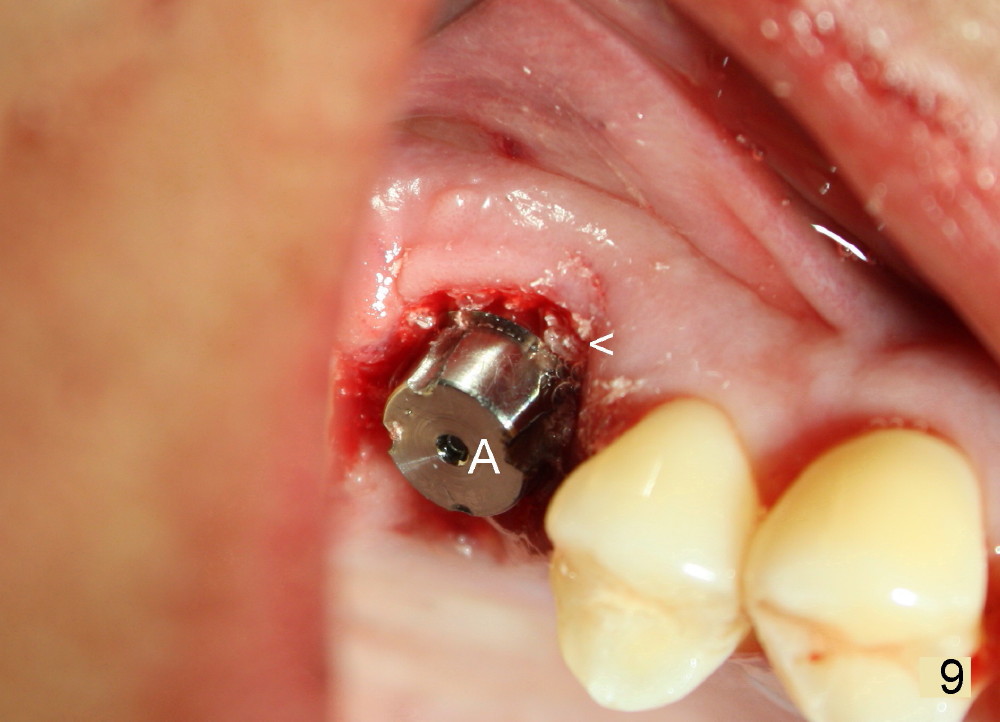

The tooth #3 has severe periodontitis with probably endodontic lesion (Fig.1,2). The patient is a 43-year-old man with apprehension of dentistry. An acute infection causes pain and tooth shift (Fig.4,5). A 7x17 mm immediate implant is planned (Fig.3). The palatal socket is shallow (Fig.6 P), corresponding to severe recessive palatal root (Fig.5 P). The osteotomy is created mainly in the buccal socket (Fig.6 B), exactly in the lingual slope of the septum. Initially osteotomes are used, followed by tap placement (Fig.7 T (4.5x20 mm at the depth of 17 mm). When the implant is placed as planned (Fig.8 I), there is more vertical contact (Fig.8 red line) than that associated with the tap (Fig.7 red line). The corresponding insertion torque is between 50 and 60 Ncm. There is only one small gap buccally, which is filled with bone graft (Fig.9 <). After the insertion of a short abutments with vertical slots (Fig.9,10 A), perio dressing is used to cover the wound. The palatal socket is expected to heal uneventfully (Fig.10 P). In fact, it does in 7 days (Fig.12 P); the bone graft in the mesiobuccal aspect is healing and stabilized (Fig.11 <). By two weeks postop, the mesiobuccal socket has healed (Fig.13 <). With removal of a diseased tooth, our body has amazing power to heal.